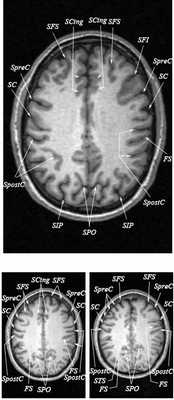

Знание анатомии мозга очень важно для правильной локализации патологических процессов. Ещё более важно оно для изучения самого мозга с помощью современных «функциональных» методов, таких как функциональная магнитно-резонансная томография (fMRI), и позитронно-эмиссионная томография. С анатомией мозга мы знакомимся ещё со студенческой скамьи и существует множество анатомических атласов, в том числе и поперечных сечений. Казалось бы, зачем ещё один? На самом деле, сравнение МРТ срезов с анатомическими приводит к множеству ошибок. Это связано как со специфическими особенностями получения МРТ изображений, так и с тем, что строение мозга очень индивидуально.

Представленная страница сайта основана на специальном изучении МРТ головного мозга здоровых лиц. Для этого изображения получали с минимальной величиной воксела (1 мм в каждом измерении), что исключало наслоения борозд. Каждая из структур прослеживалась в трёх реконструированных плоскостях путём её выделения с помощью компьютерной программы. Мы рассматривали различные анатомические варианты, что обсуждается в работе. В результате, учитывая вариабельность строения мозга, подобран условно «стандартный» мозг. Поскольку на сайте нереально представить 128 срезов в каждой из основных плоскостей, мы ограничились только каждым пятым срезом. Основные срезы в поперечной плоскости даны без наклона назад (угол 0º). Под ними для представления о изменении соотношения анатомических структур демонстрируются срезы, выполненные на тех же уровнях, но с наклонами назад -15º и -30º.

Список сокращений

Борозды

Междолевые и срединные

SC - центральная борозда

FS - Сильвиева щель (латеральная борозда)

SPO - теменно-затылочная борозда

SCing - поясная борозда

SpreC - предцентральная борозда

SFS - верхняя лобная борозда

SpostC - постцентральная борозда

SIP - внутритеменная борозда

STS - верхняя височная борозда

Поперечные (аксиальные) МРТ срезы головного мозга